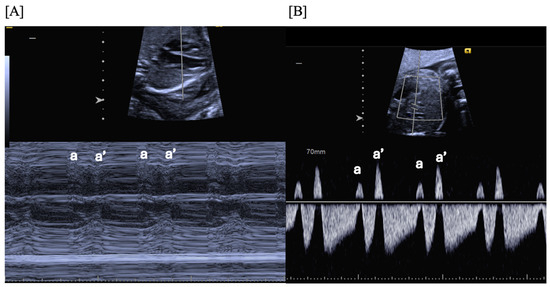

- Long VA SVT (Figure 4) demonstrates a VA interval that is more than half of the VV interval (VA:AV ratio > 1). Long VA SVT includes EAT and PJRT. A distinguishing feature of EAT is tachycardia termination with ventricular contraction. Long VA SVT may occur as early as 12 weeks of gestation. Because long VA tachycardias have slower rates, they are less likely to cause hydrops.